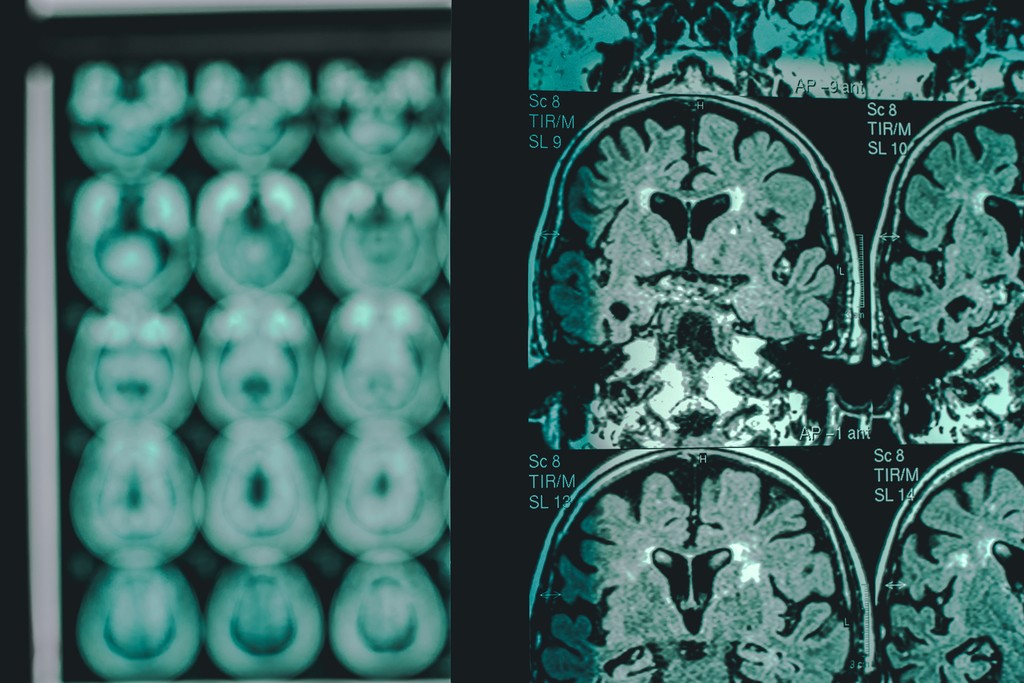

Zabúdanie, odkladanie vecí, dezorientácia. Každé štyri sekundy pribudne nový prípad Alzheimerovej choroby. Na liek čakajú milióny ľudí. V roku 2030 bude svet potrebovať miliardy eur na starostlivosť o týchto pacientov.

Predstavte si však, že by stačilo podať jednu injekciu a choroba by sa neprejavila. Slovenský vedec Michal Novák je len krok od vyvinutia účinnej vakcíny, ktorá chorobu prakticky eliminuje.

Zakladateľ Neuroimunologického ústavu SAV, Slovenskej Alzheimerovej spoločnosti a tiež nadácie Memory našiel bielkovinu tau, ktorá je zodpovedná za deštrukciu mozgu.

„Trvalo štyri roky, kým sme to rozanalyzovali, že tau proteín je schopný hovoriť so zdravými bunkami a meniť ich na choré. A tým sme objavili celý základný reťazec,“ konštatoval.

Teraz má jeho tím za sebou úspešnú prvú fázu klinických skúšok prvej aktívnej vakcíny s liečivým účinkom proti Alzheimerovej chorobe na svete. Podľa Nováka ide o značne bezpečný systém a verí, budú môcť začať s preventívnym očkovaním.

„Vakcína je schopná ovplyvňovať neurodegeneračné procesy v mozgu pacientov. Teraz pripravujeme ďalšiu fázu klinického skúmania, ktorá by mala potvrdiť účinnosť,“ vysvetlil člen tímu Norbert Žilinka.